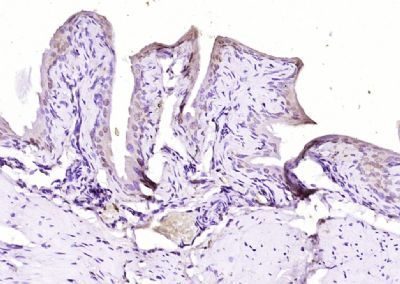

面肩肱型肌营养不良症相关蛋白FRG1抗体

目录号:bs-13215R

商品规格:200ul